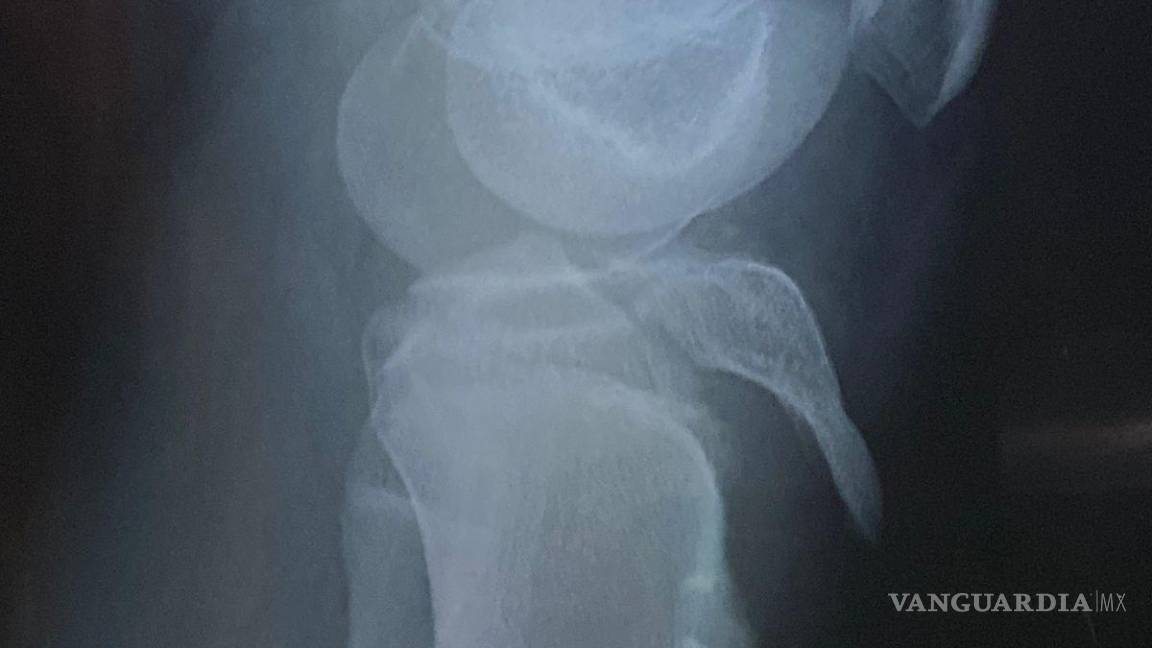

El menor participaba en prácticas para una actividad llamada “olimpiada” cuando resultó con una grave lesión en la rodilla que requirió cirugía para la colocación de tornillos.

$!La cirugía del estudiante implicó la colocación de tornillos en la tibia, costos que inicialmente cubrieron los tutores.